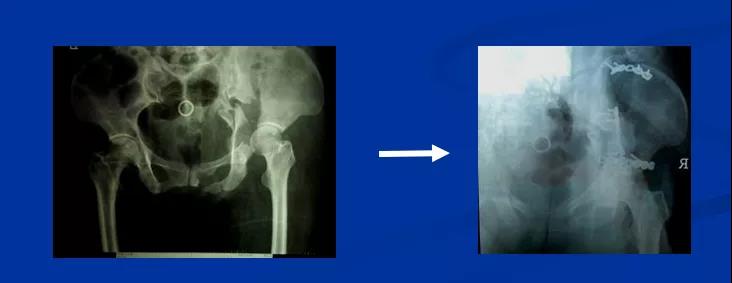

——典型案例——

微创插板病历后路有限切开,结合前路微创插板内